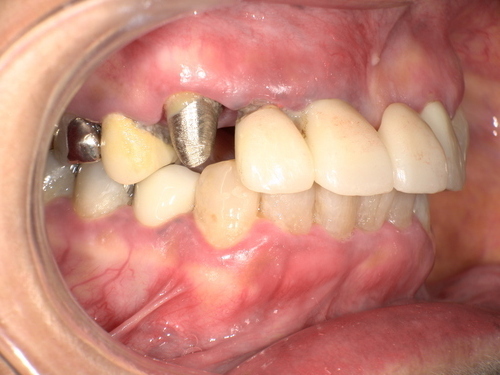

歯の詰め物(金属・銀歯)や薬剤の影響

古い銀歯や金属製クラウンから金属イオンが溶出し、口腔粘膜との接触でアレルギー反応が生じる場合があります。クロム・ニッケル・金・水銀などが原因物質となることがあり、金属アレルギーのある人は特に注意が必要です。